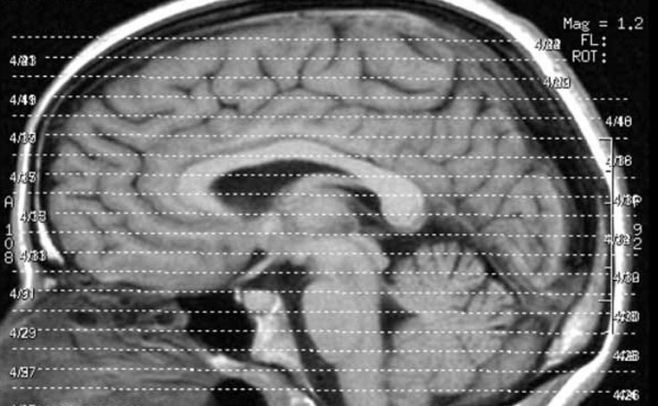

En este trabajo, los investigadores estudiaron al grupo de niños y adolescentes mediante resonancias magnéticas y descubrieron la relación entre los cambios en el grosor cortical cerebral y los cambios en el desarrollo del coeficiente de inteligencia.